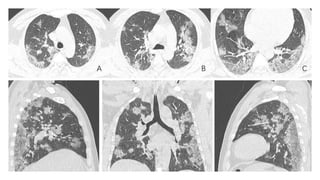

Radiology.